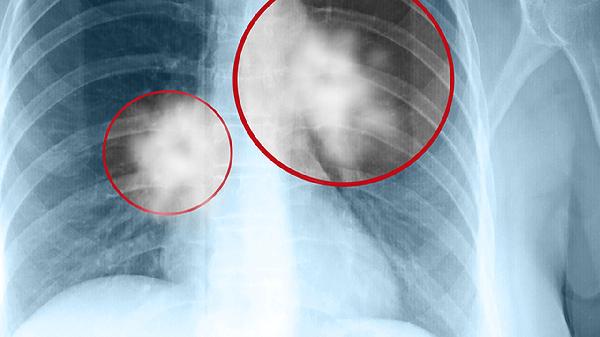

肺泡蛋白沉积症是一种罕见的肺部疾病,主要特征是肺泡内异常积聚蛋白质和脂质物质,导致呼吸困难、咳嗽和低氧血症。治疗方法包括全肺灌洗、药物治疗和支持性疗法。

肺泡蛋白沉积症虽然罕见,但通过早期诊断和综合治疗,可以有效控制症状,改善患者的生活质量。定期体检和健康管理是关键,对于高风险人群,更应加强预防和监测。